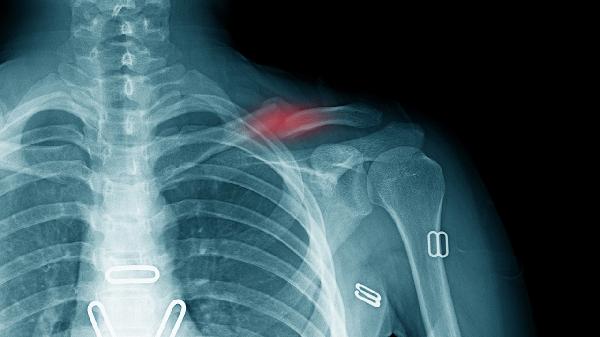

锁骨骨折手术后多久可以正常活动 锁骨骨折手术后要注意些什么

锁骨骨折手术后一般需要6-8周恢复正常活动,具体恢复时间受到骨折类型、固定方式、康复训练、年龄体质和并发症等因素影响。

线性骨折恢复较快,粉碎性骨折需更长时间。骨折线越复杂,骨痂形成速度越慢,过早活动可能导致内固定失效。术后需定期复查X线确认愈合进度,粉碎性骨折患者需延长制动期至8-10周。